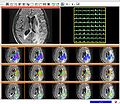

We want to integrate the currently available MRSI quantitation routines with the SIVIC Slicer interface developed at the UCSF. More specifically we want to integrate the previously developed signal processing routines (Fig. 1) into the svk library of the SIVIC framework, and realize the joint display of metabolic maps (Fig. 2) and spectral information (Fig. 3) within the current prototype of the Slicer module.

• We implemented a basic quantification algorithm (Fig. 4) integrating over predefined spectral regions and made progress towards implementing the other fitting routines.

• Metabolic maps generated in Slicer can now be displayed (Fig. 4).

• The display of individual spectra in Slicer now also supports multiple traces from the spectral fitting (Fig. 5).